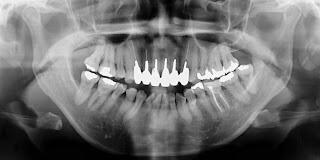

↑レントゲン写真。

歯列矯正する前に、まずは昔の出っ歯の歯並びの状態を再現し、3Dスキャンしたり、レントゲン写真を撮影したりする事になりました。